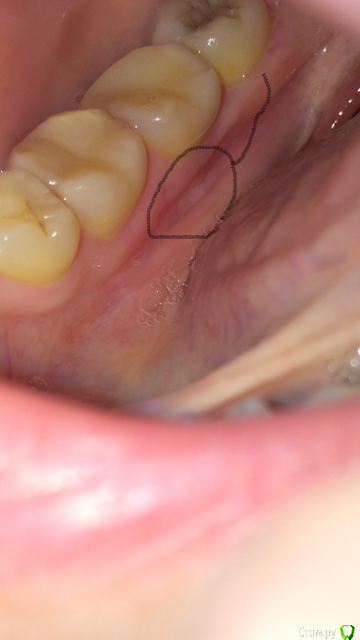

также болела область с внутренней стороны десны возле примерно  6, 7, 8 зубов справа снизу. Под 7 зубом что-то белое виднеется.

Прикладываю фото.

post-50717-0-42934100-1525732500_thumb.png